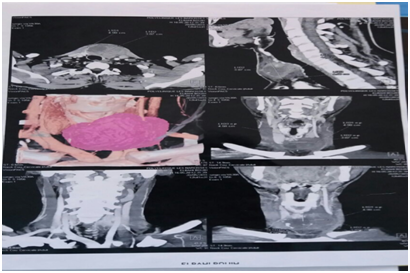

We report the case of the 44-year-old patient, who for 5 years showed a cervical swelling gradually increasing in volume and subsequently compressive, with an alteration in the general condition, with cervical ultrasound completed by cervical CT In preoperative procedures: nodular heterogeneous hypoechoic goitre of 38* 49* 4 mm with calcifications 4C(according to the 2015 criteria of the American Cancer Society) , with compression and repression of left jugular carotid and trachea, absence of cervical adenopathies (Figure 1). The gesture consisted of a total thyroidectomy, the anatomopathological study showed a malignant proliferation, little differentiated and infiltrating, presence of vascular emboli, peri-nervous entrapment and capsular effraction, the immunohistochemical study showed a carcinoma Little differentiated and infiltrating, classified pT3NxMx, the evolution was marked at day 5 of postoperative by recurrence of the cervical swelling with compressive signs to the type of dysphagia and dysphonia, the clinical examination finds: a firm anterior cervical mass painful An ultrasound was performed in which the bulk of the bilateral clavicular and bilateral cerebral regions that could be associated with lymphadenopathy were examined, a cervical computed tomography (Figure 2) had shown a large tumorous process from the cervico-mediastinal orifice to the hyoid bone infiltrating the soft tissue without adenopathy, after three days of development the patient died as a result of Complications and tumor hemorrhage.

Figure 2 CT scan showing a large cervical tumor process infiltrating soft tissues in relation to recurrence.